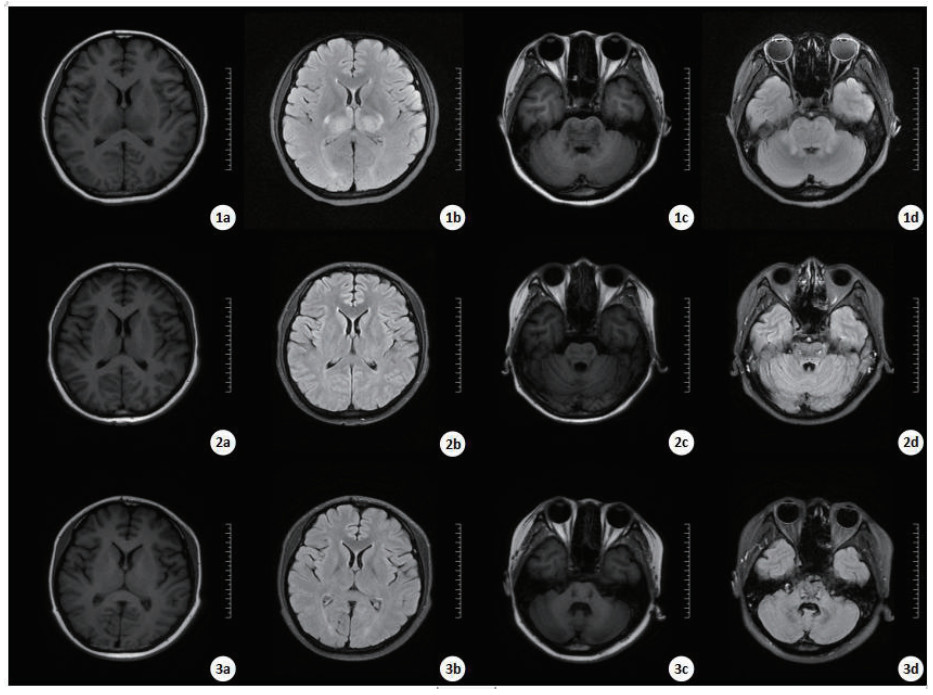

2 典型病例病例1:患者男,21岁,以“口服敌草快100 mL 5 h”代主诉入院,既往体健。体格检查:体温37.5℃,脉搏130次/min,呼吸30次/min,血压120/82 mmHg(1 mmHg=0.133 kPa),烦躁,对答不切题,定向障碍,查体不配合,心肺听诊未见明显异常,病理征阴性。实验室检查:血常规:白细胞(WBC)24.16×109/L、红细胞(RBC)5.06×1012/L、血小板(PLT)231×109/L,中性粒细胞百分比(N%) 91.6%。肝功能:谷草转氨酶(AST)43 U/L,谷丙转氨酶(ALT)25 U/L。肾功能:肌酐(Cr)105 μmol/L,肾小球滤过率63.965 mL/min/1.73 m2。动脉血气分析:pH 7.482,动脉血氧分压(PO2)89.4 mmHg,二氧化碳分压(PCO2)30.50 mmHg,实际碳酸氢根(HCO3-)22.80 mmol/L,乳酸1.6 mmol/L。入院查头颅CT未见明显异常(见图 1)。距服药时间36出现氧和不能维持,行气管插管接呼吸机辅助通气,46 h出现抽搐、全身强直性阵挛发作,查体见双侧瞳孔散大固定,牙关紧闭,全身肌张力增强、角弓反张,给予地西泮、苯巴比妥抗癫痫药物应用后癫痫样发作症状可被控制,但出现血压下降至60~80/30~40 mmHg,给予补液、升压药物应用。61 h后行头颅CT检查示:丘脑、脑干密度减低。脑干梗死,脑弥漫性肿胀。自动离院后死亡。

| 入院时头颅CT(a、b),入院61 h后头颅CT(c、d)示:脑实质灰白质分界不清,脑沟、脑裂变浅,部分脑池变窄,枕大池显示不清,丘脑、脑干密度减低,小脑扁桃体似向下移位,小脑幕及大脑镰密度稍增高,中线结构居中。 图 1 病例1的CT结果 Fig 1 CT results of Case 1 |